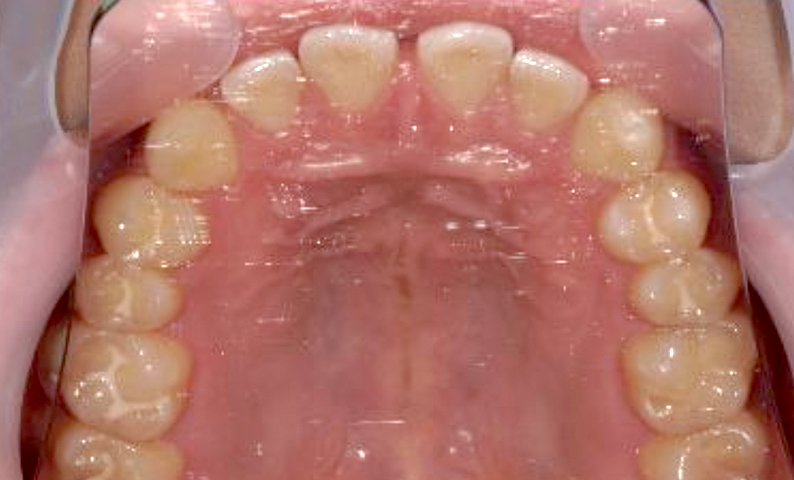

症例_001 前歯「すきっ歯」症例

治療期間:9ヶ月金額:51万円+税20代女性すきっ歯